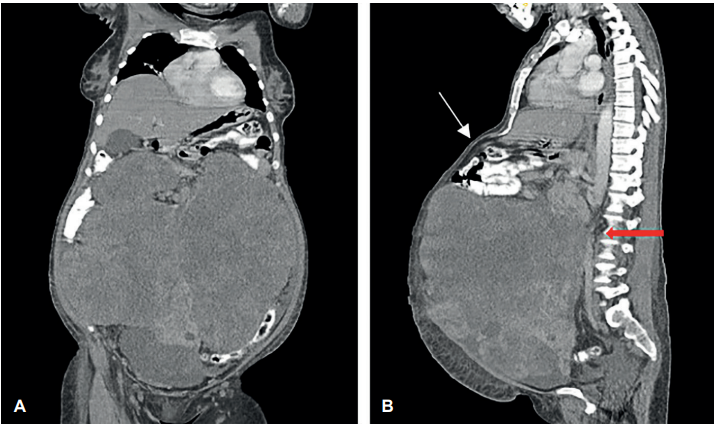

Figura 1. A. Corte coronal de la tomografía abdominopélvica que muestra una masa gigante que ocupa casi la totalidad de la cavidad abdominal. B. Corte sagital de la tomografía abdominopélvica que evidencia la severa compresión y desplazamiento cefálico de las asas intestinales delgadas (flecha blanca) y la compresión de las estructuras retroperitoneales (flecha roja).

Se presenta el caso de una mujer de 51 años, sin antecedente de NF1, que consultó por un cuadro de dolor y aumento del perímetro abdominal de 7 meses de evolución. El examen físico y los estudios de imágenes revelaron una gran masa intraabdominal, sólida y heterogénea (Figura 1). La paciente fue intervenida encontrándose un tumor de 35 cm y 14,5 Kg de peso, con compromiso del fondo úterino, anexo derecho, ciego, apéndice e intestino delgado. Se realizó resección en bloque del tumor (Figura 2), con anexohisterectomía, omentectomía, apendicectomía, cequectomía parcial, resección del segmento de intestino delgado adosado al tumor y reconstrucción del transito digestivo con anastomosis latero-lateral. El reporte de la patología informó un TMVNP.